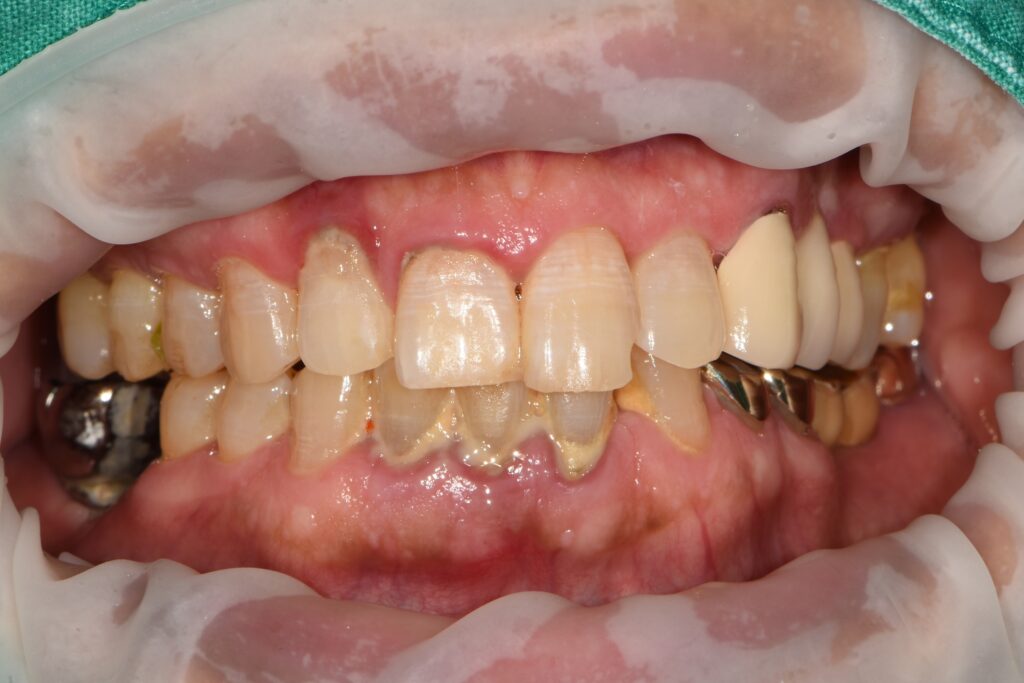

60대 남성 환자분이셨습니다.

특별한 전신 질환도 없고, 평소 큰 문제 없이 지내시다가

예전에 씌워둔 왼쪽 어금니가 아파서 병원을 찾으셨습니다.

파노라마 촬영과 구내 사진으로 전체를 살펴보았습니다.

그 결과는 조금 달랐습니다.

문제는 특정 치아 하나가 아니라,

전반적인 잇몸 상태였습니다.

치조골이 전반적으로 낮아져 있는

수평적 골 소실이 동반된

만성 복합 치주염 소견이 확인되었습니다.

즉,

아픈 치아 하나만 고친다고 끝나는 상황이 아니었습니다.